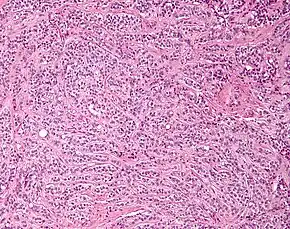

Micrograph of a Sertoli cell tumour. H&E stain.

A Sertoli cell tumour, also Sertoli cell tumor (US spelling), is a sex cord–gonadal stromal tumour of Sertoli cells. They can occur in the testis or ovary. They are very rare and generally peak between the ages of 35 and 50. They are typically well-differentiated and may be misdiagnosed as seminomas as they often appear very similar.[1]

Microscopy and immunohistochemistry are the only way to give a definitive diagnosis, especially when there is a suspected seminoma.[3]